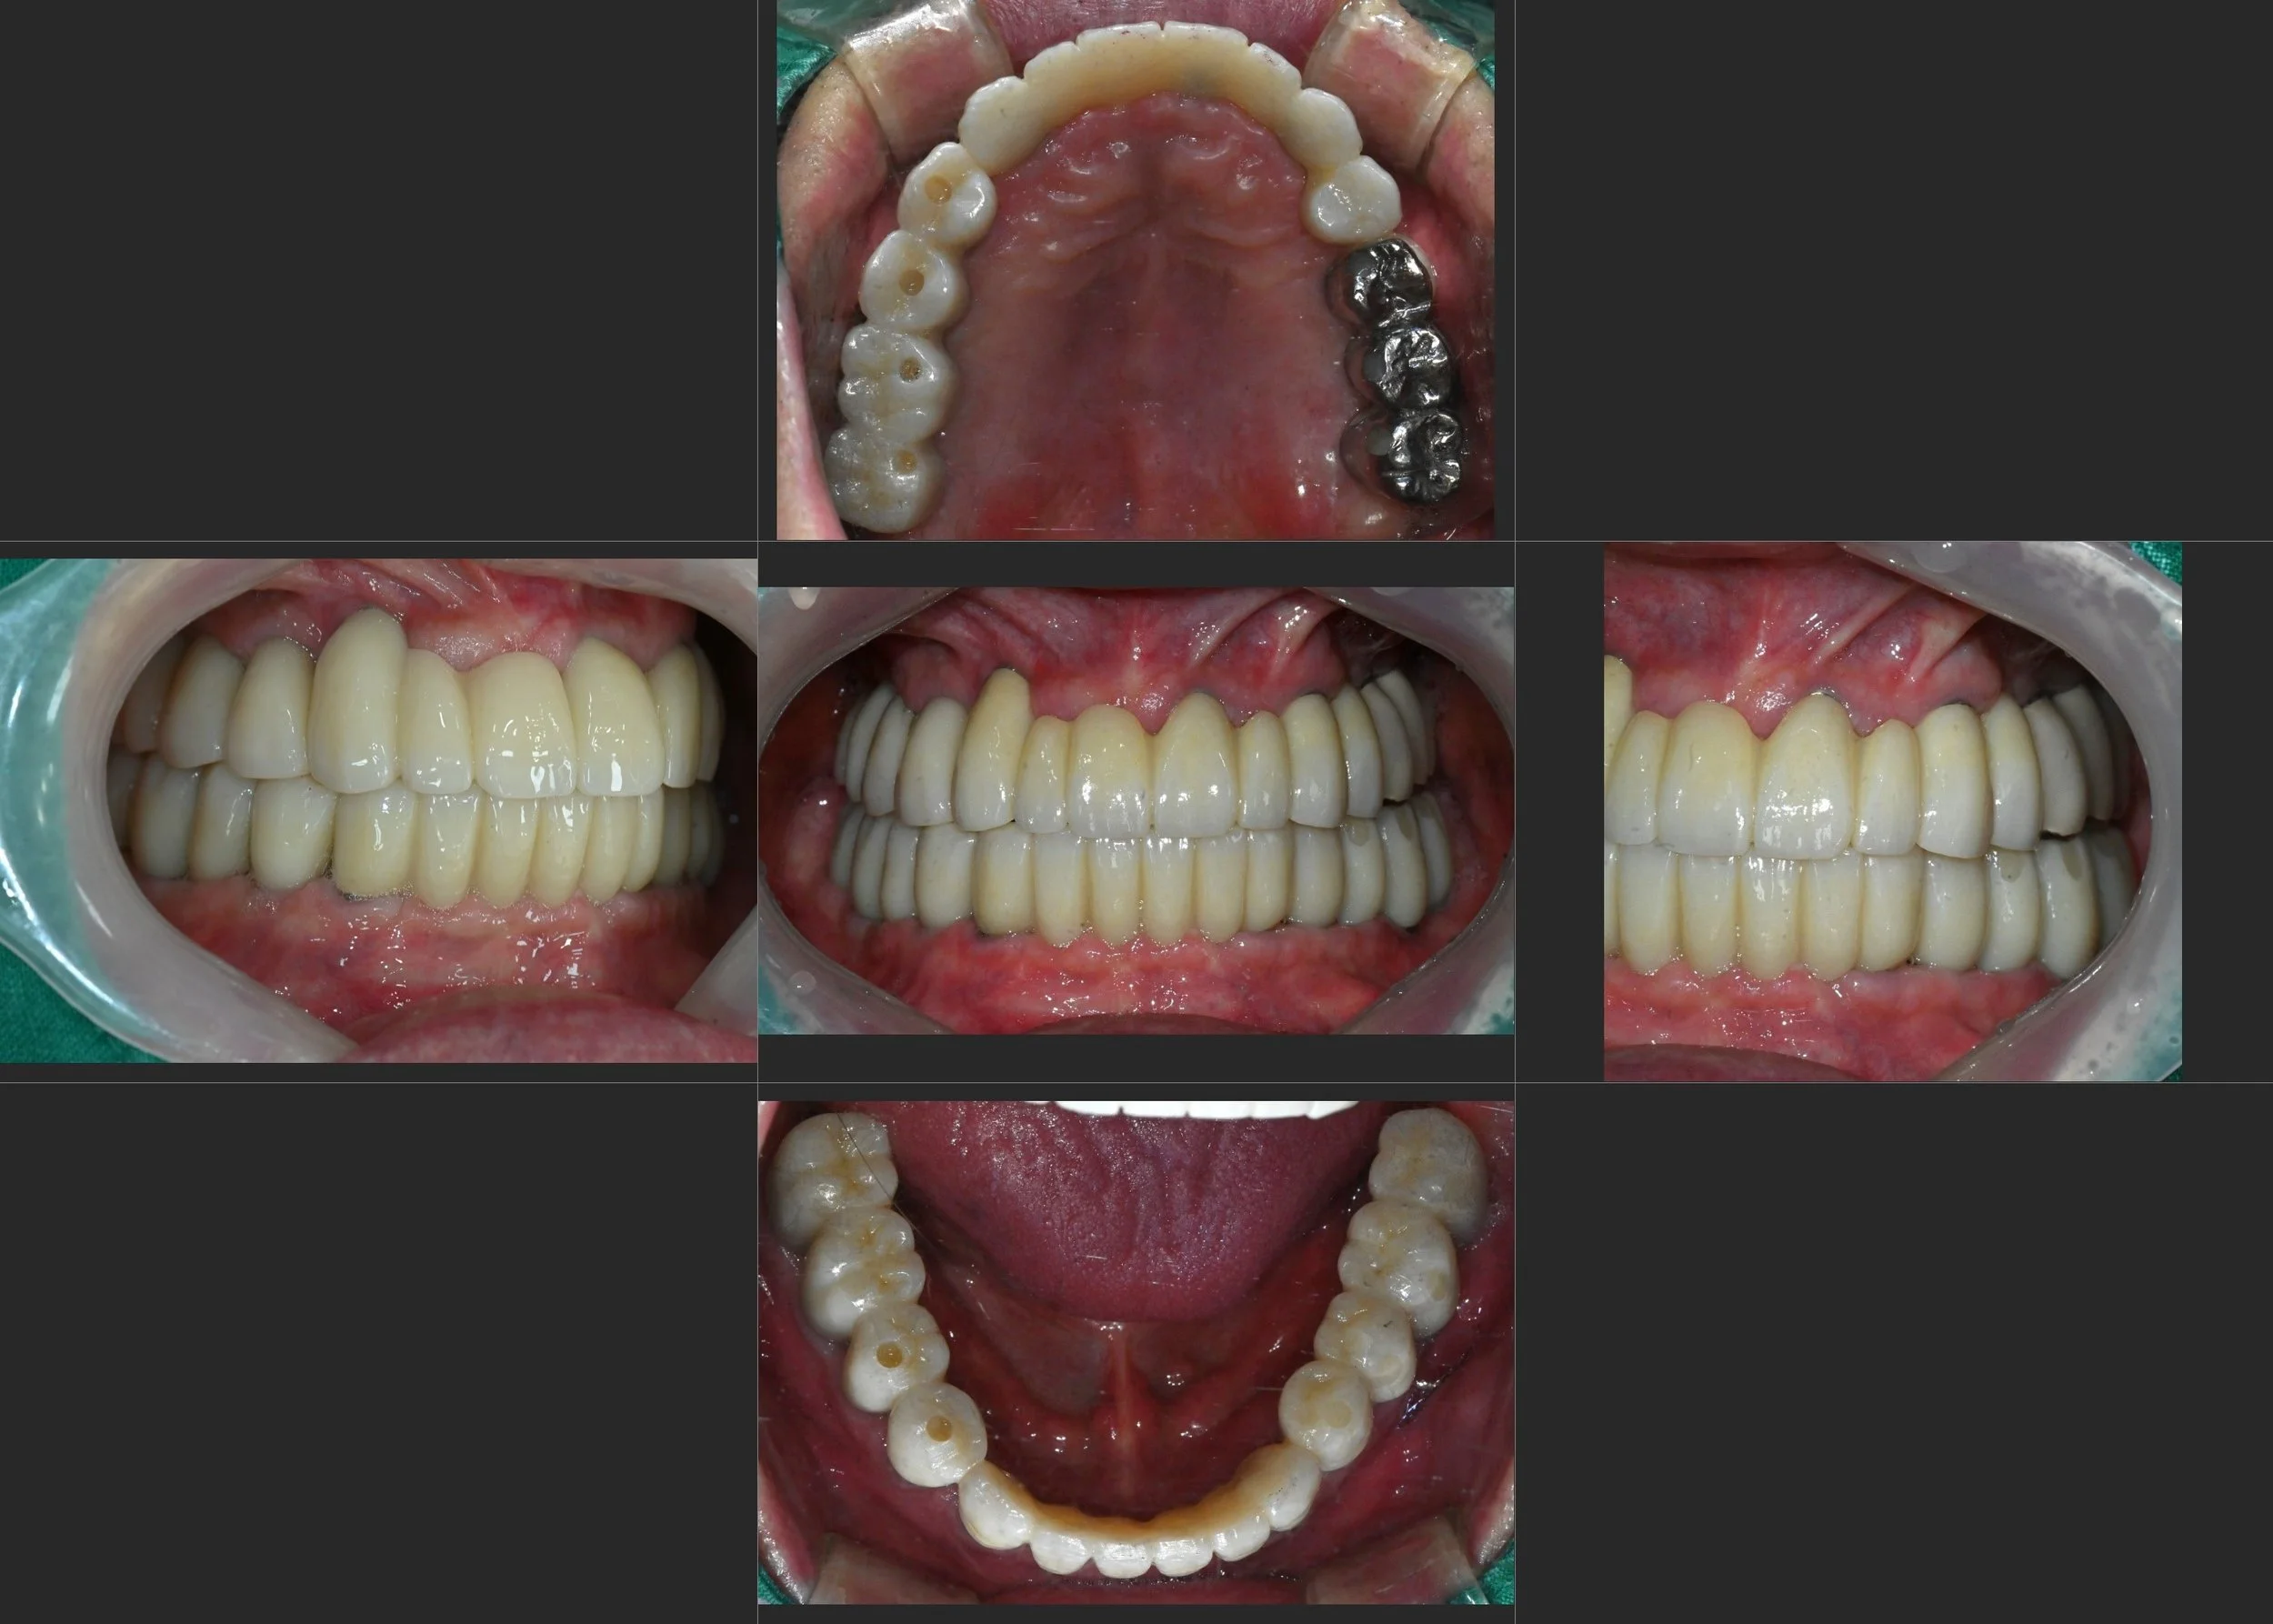

INTRA ORAL - AFTER

3. Final Delivery: Precision-milled, full-arch fixed bridges were delivered. These restorations were designed to provide maximum durability for mastication while restoring the lip support and aesthetics that the patient had lost during his years of denture use.

The transition from a failing, removable state to a fixed, full-arch solution has provided the patient with a level of comfort and confidence he had not experienced in decades.